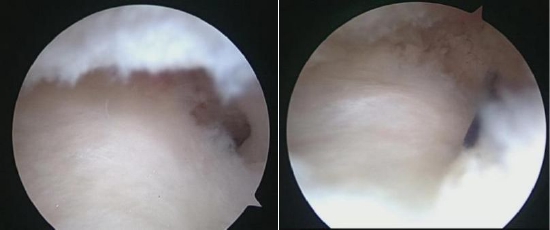

以肩袖损伤的病人为例,很多患者可以进行肩关节镜微创手术来进行治疗,效果非常好。关节镜手术是将具有照明装置的透镜金属管通过很小的切口由自然腔隙进入关节腔内,可以在高清显示器监视下非常直观的观察关节腔内的病变情况和严重程度,全面检查和清理修复病损,是一种兼具诊断和治疗两种功能的微创技术。

1、损伤性疾患:前后交叉韧带损伤(重建)、半月板损伤(切除、部分切除、缝合及成形术、半月板移植)、关节软骨损伤、关节内骨折的复位与固定术(如:前后叉撕脱骨折关节镜下复位固定)。

2、膝关节疾病:腘窝囊肿、膝关节滑膜炎、类风湿关节炎(滑膜组织活检及滑膜切除术);关节异物、晶体、碎片、游离体等的清(摘)除术;软骨或骨软骨病变的成形、移植或清理;髌骨轴线的矫正术;骨赘或肿瘤切除;关节粘连和僵硬的松解。